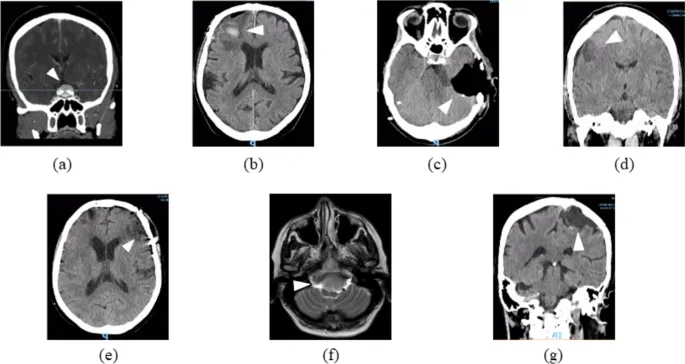

Рисунок 2: Предоперационная нейровизуализация пациентов с опухолями головного мозга, проходящих NF-реабилитацию. Легенда: a Пациент 1: Акссиальная КТ-скан, показывающая менингиому бугорка седла (стрелка). b Пациент 2: Коронарная КТ, показывающая левую переднюю парасагиттальную менингиому. c Пациент 3: Коронарная КТ правой петрокливальной менингиомы. d Пациент 4: Акссиальная КТ, изображающая левую оперкулярную глиому. e Пациент 5: Акссиальная КТ-скан правой лобной менингиомы с кровоизлиянием. f Пациент 6: Коронарная Т2-взвешенная МРТ менингиомы foramen magnum. g Пациент 7: Коронарная КТ-скан правой роландической менингиомы. Примечание: Стрелки указывают на локализацию поражения. Изображения зеркально отражены для удобства чтения. Все изображения анонимизированы и используются с согласия пациентов.